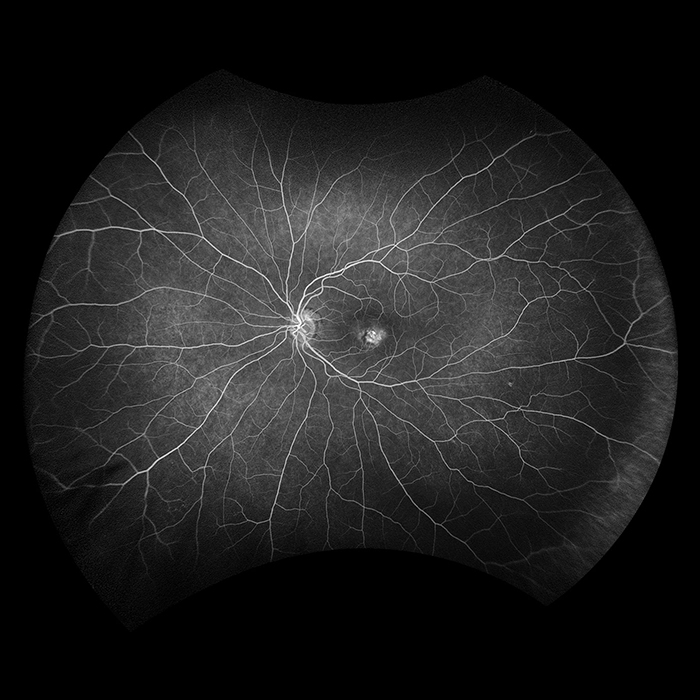

Fluorescein Angiography ultra-widefield, ultra-high resolution angiography, enables a simultaneous pole-to-periphery view of the retina. This allows the entire retinal vasculature to be imaged during the dye transit by a non-contact method. This supports practitioners in diagnosing ocular pathology that may first present in the periphery of the retina, resulting in better patient outcomes.